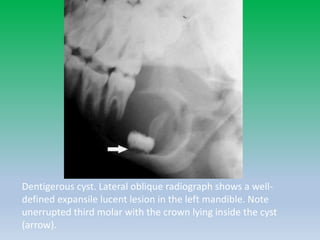

Dentigerous Cyst

• Most common developmental odontogenic cyst.

• 3rd-4th decade of life.

• Forms around the crown of an unerrupted tooth as fluid

collects between layers of epithelium or between the

epithelium and enamel.

• Dentigerous cysts can vary in size but have the potential

to grow large enough to cause significant expansion of

the jaw and displacement of adjacent teeth; however,

resorption of the root apex is uncommon.

Dentigerous cyst. Lateral oblique radiograph shows a well-

defined expansile lucent lesion in the left mandible. Note

unerrupted third molar with the crown lying inside the cyst

(arrow).